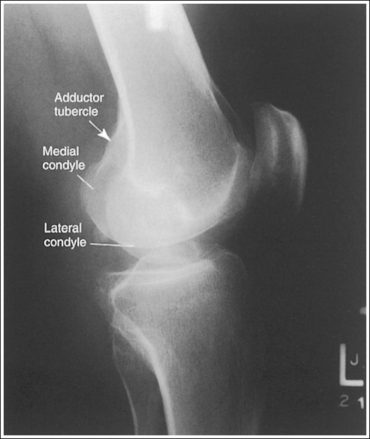

• Distinguishing lateral and medial condyles. The first step you should take when evaluating an image on which the distal condylar surfaces are not aligned is to determine which condyle is the lateral and which is the medial. The most reliable method for identifying the medial condyle is to locate the rounded bony tubercle known as the adductor tubercle. It is located posteriorly on the medial aspect of the femur, just superior to the medial condyle. The size and shape of the tubercle are not identical on every patient, although this surface is considerably different from the same surface on the lateral condyle, which is smooth. Once the adductor tubercle is located, the medial condyle is also identified. Another difference between the medial and lateral condyles is evident on their distal articulating surfaces. The distal surface of the medial condyle is convex, and the distal surface of the lateral condyle is flat.